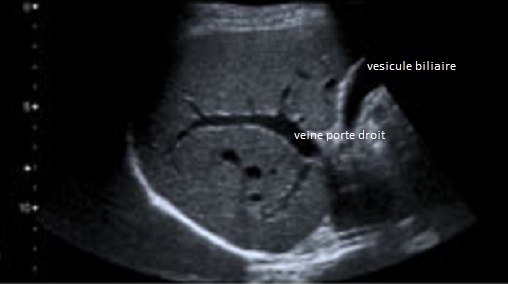

Coupe intercostale de

la ligne axilaire anterieuse droit . On en

voyait foie droit , branche droit de la veine porte

, vesicule biliaire et parfois artere hepatique |

Image echographique normale

du foie droit en coupe intercostale de

la ligne axilaire anterieuse droit ( long sagitale -

vesiculaire ) . On en

, vesicule biliaire et artere hepatique |